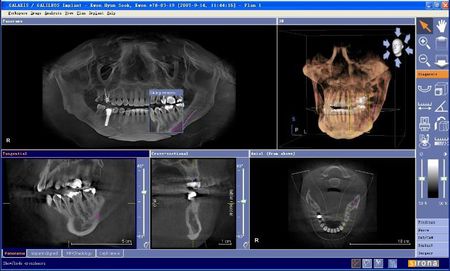

4)CT

電子計(jì)算機(jī)X線體層攝影,簡(jiǎn)稱(chēng)CT。CT檢查的優(yōu)點(diǎn)是能避免影像重疊,使圖像非常清晰,具有很高的密度分辨力。對(duì)頜骨,牙齒進(jìn)行計(jì)算機(jī)斷層掃描,重建三維圖像,可多角度再現(xiàn)頜骨,牙齒內(nèi)部結(jié)構(gòu),各個(gè)組織間的關(guān)系。特別是對(duì)頜面部腫瘤的位置,范圍能提供較準(zhǔn)確的信息。